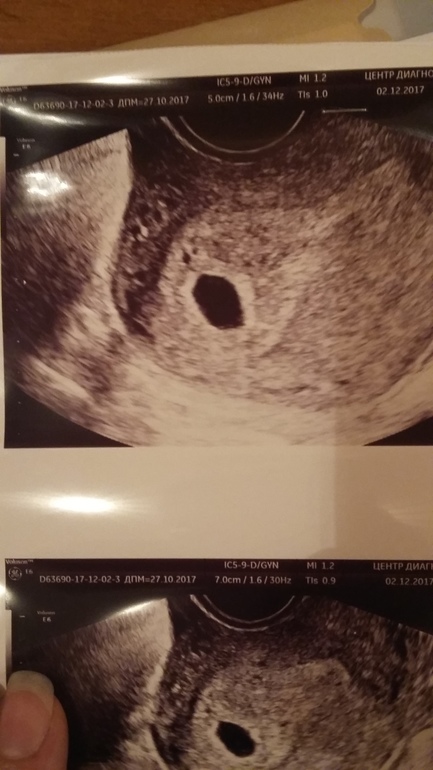

Запись на первое узи и вот она наше маленькое но такое большое счастье!!!